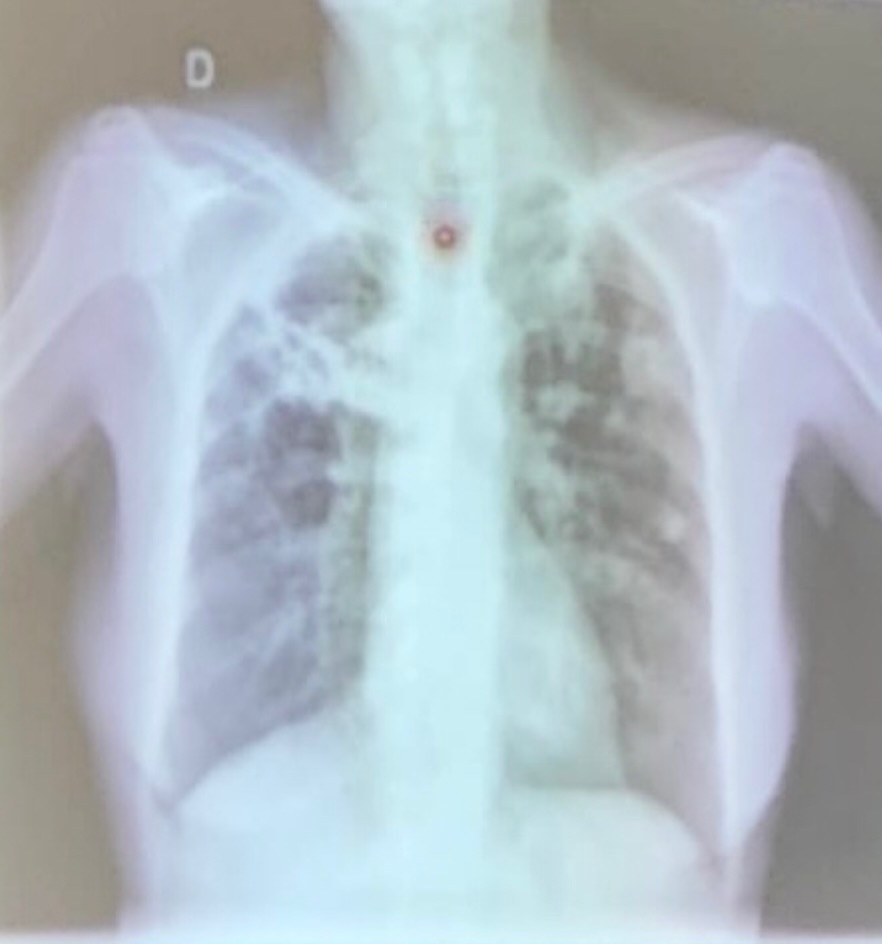

cardiomegalia